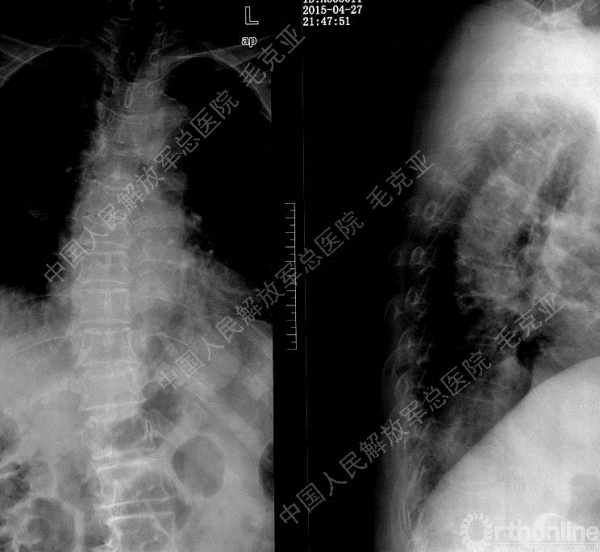

毛克亚:新型弯角椎体增强装置的研制与临床应用研究

导语:随着社会老龄化的不断加速,骨质疏松性椎体压缩骨折作为一种普遍存在的老年骨科疾病已经成为现今骨科界的一个热点话题。传统的保守疗法治疗效果不佳,而现有的椎体增强技术又具有多种风险和缺陷。针对这种现状,中国人民解放军总医院毛克亚教授提供了一种新的解决方法。